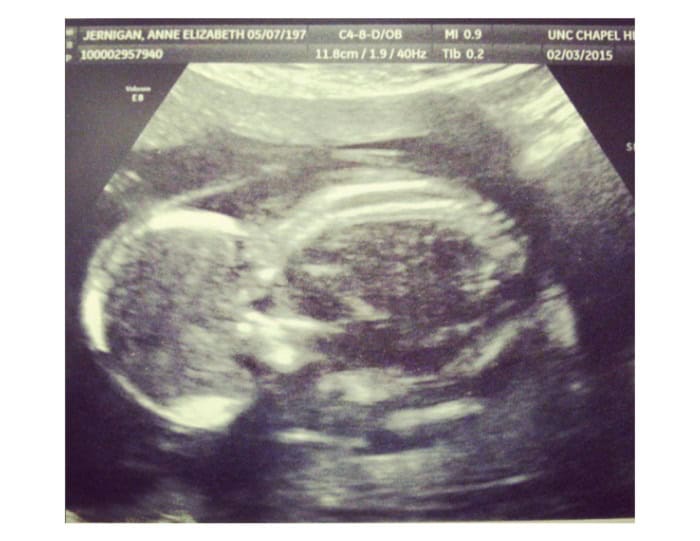

Το υπερηχογράφημα της Vivianne. Η Φωτογραφία είναι ευγενική προσφορά της οικογένειας Jernigan.

Ο γιατρός τους ρώτησε τι θα έκαναν με το κοριτσάκι — και εκείνοι χωρίς να διστάσουν, επέλεξαν και για αυτό τη ζωή. Συναντήθηκαν με γιατρούς που αναλαμβάνουν παιδιά με Τρισωμία 18 και έκαναν σχέδια για το πώς θα φροντίσουν τη Βιβιάν όταν γεννηθεί, αντί να την αφήσουν να πεθάνει. Αλλά δυστυχώς, κατά τη διάρκεια ενός υπερήχου στις 18 εβδομάδες και 5 ημέρες, διαπιστώθηκε ότι η Vivianne δεν είχε πλέον καρδιακό παλμό.